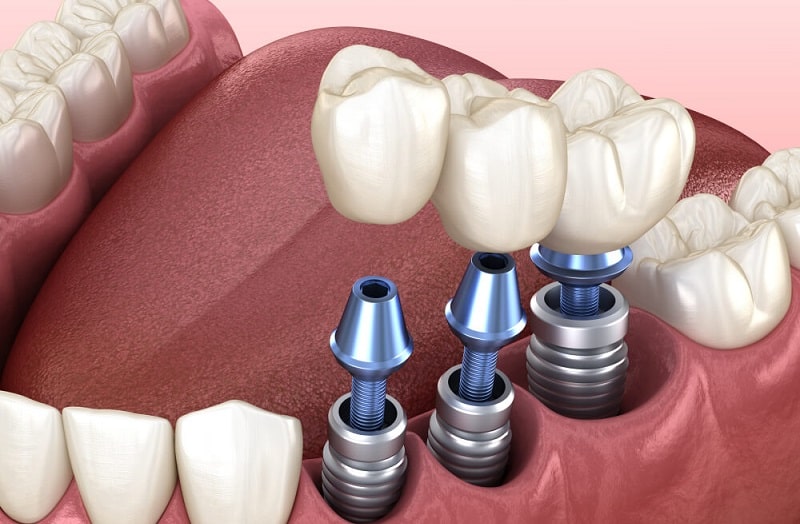

انتخاب بهترین ایمپلنت دندان به عوامل مختلفی بستگی دارد؛ از شرایط فک و لثه گرفته تا برند، تخصص پزشک و بودجه شما. در ادامه مهمترین نکات را بهصورت کاربردی مرور میکنیم:

4) جنس ایمپلنت

اکثر ایمپلنتها از تیتانیوم ساخته میشوند (سازگاری بالا با بدن). برخی مدلهای جدید سرامیکی (زیرکونیا) نیز وجود دارند که برای افراد حساس به فلز مناسبترند.

- جنس تیتانیوم خالص یا آلیاژ تیتانیوم گرید بالا (سازگار با بدن و ضدحساسیت)

- سازگاری زیستی بالا (Biocompatible) و جوش خوردن سریع با استخوان

- سطح زبر و پیشرفته برای افزایش سرعت اُسواینتگریشن (جوش خوردن با استخوان)

- طراحی رزوهای استاندارد برای ثبات اولیه قوی